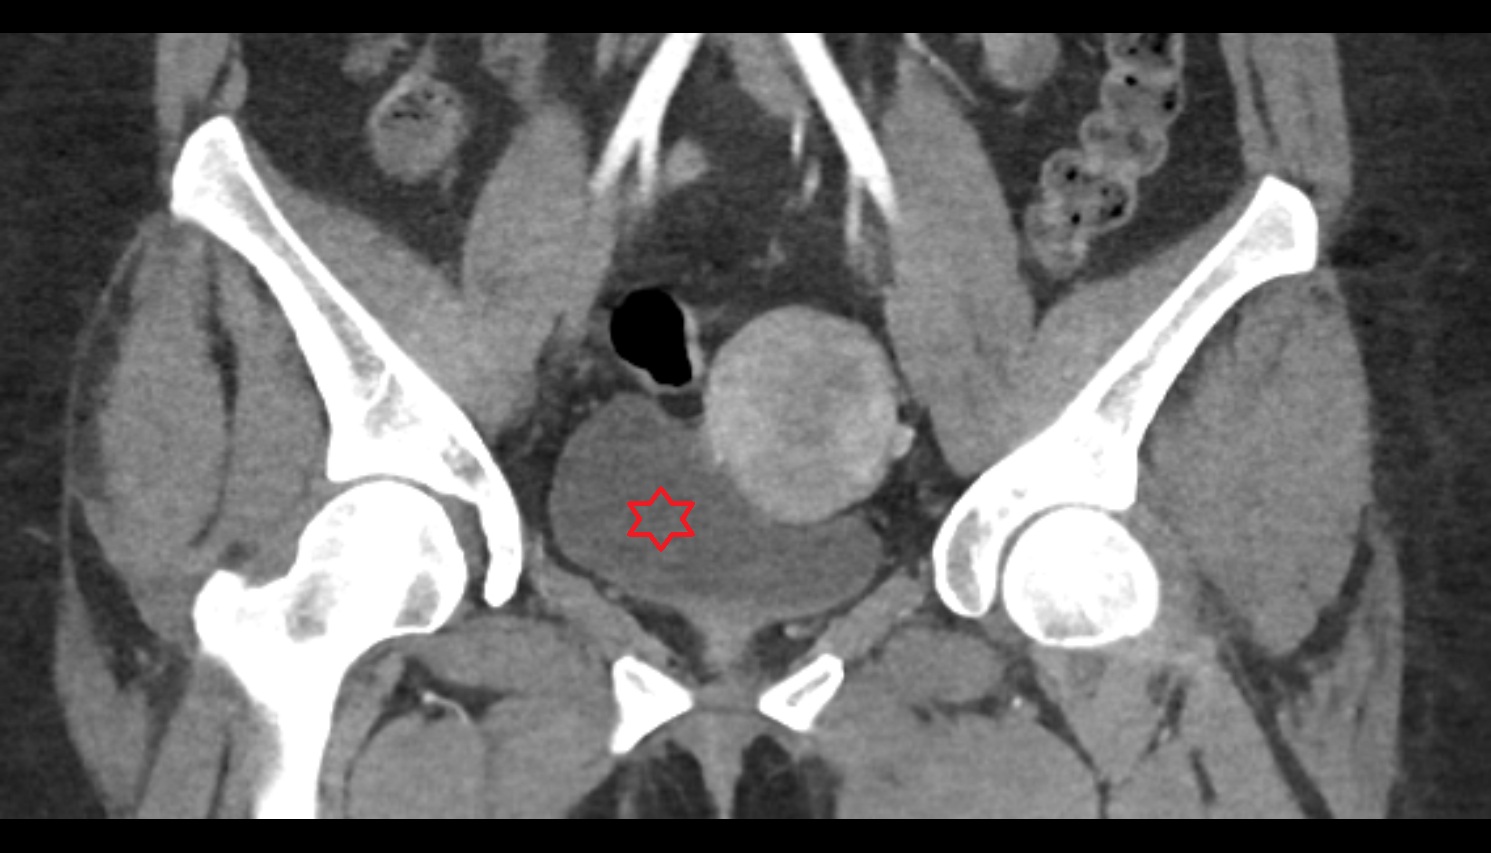

- Head of femur

- Acetabulum

- Sacrum

- Sacroiliac joint